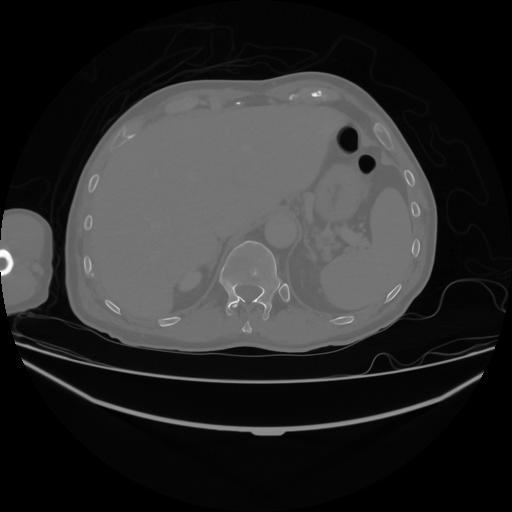

5 CUERPO,CE,Vol,1.0,CUERPO,,